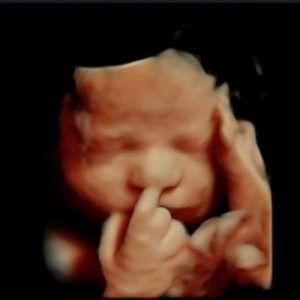

3D Υπερηχογράφημα